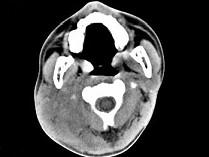

问题 男,17岁,自诉鼻涕中带血3个月,伴耳闷、听力减退,无发热。如图所示鼻咽部病灶最可能的诊断为 ( )

选项 A、小唾液腺混合瘤 B、鼻咽部淋巴组织增生 C、鼻咽部恶性淋巴瘤 D、鼻咽癌 E、咽旁脓肿

答案 D